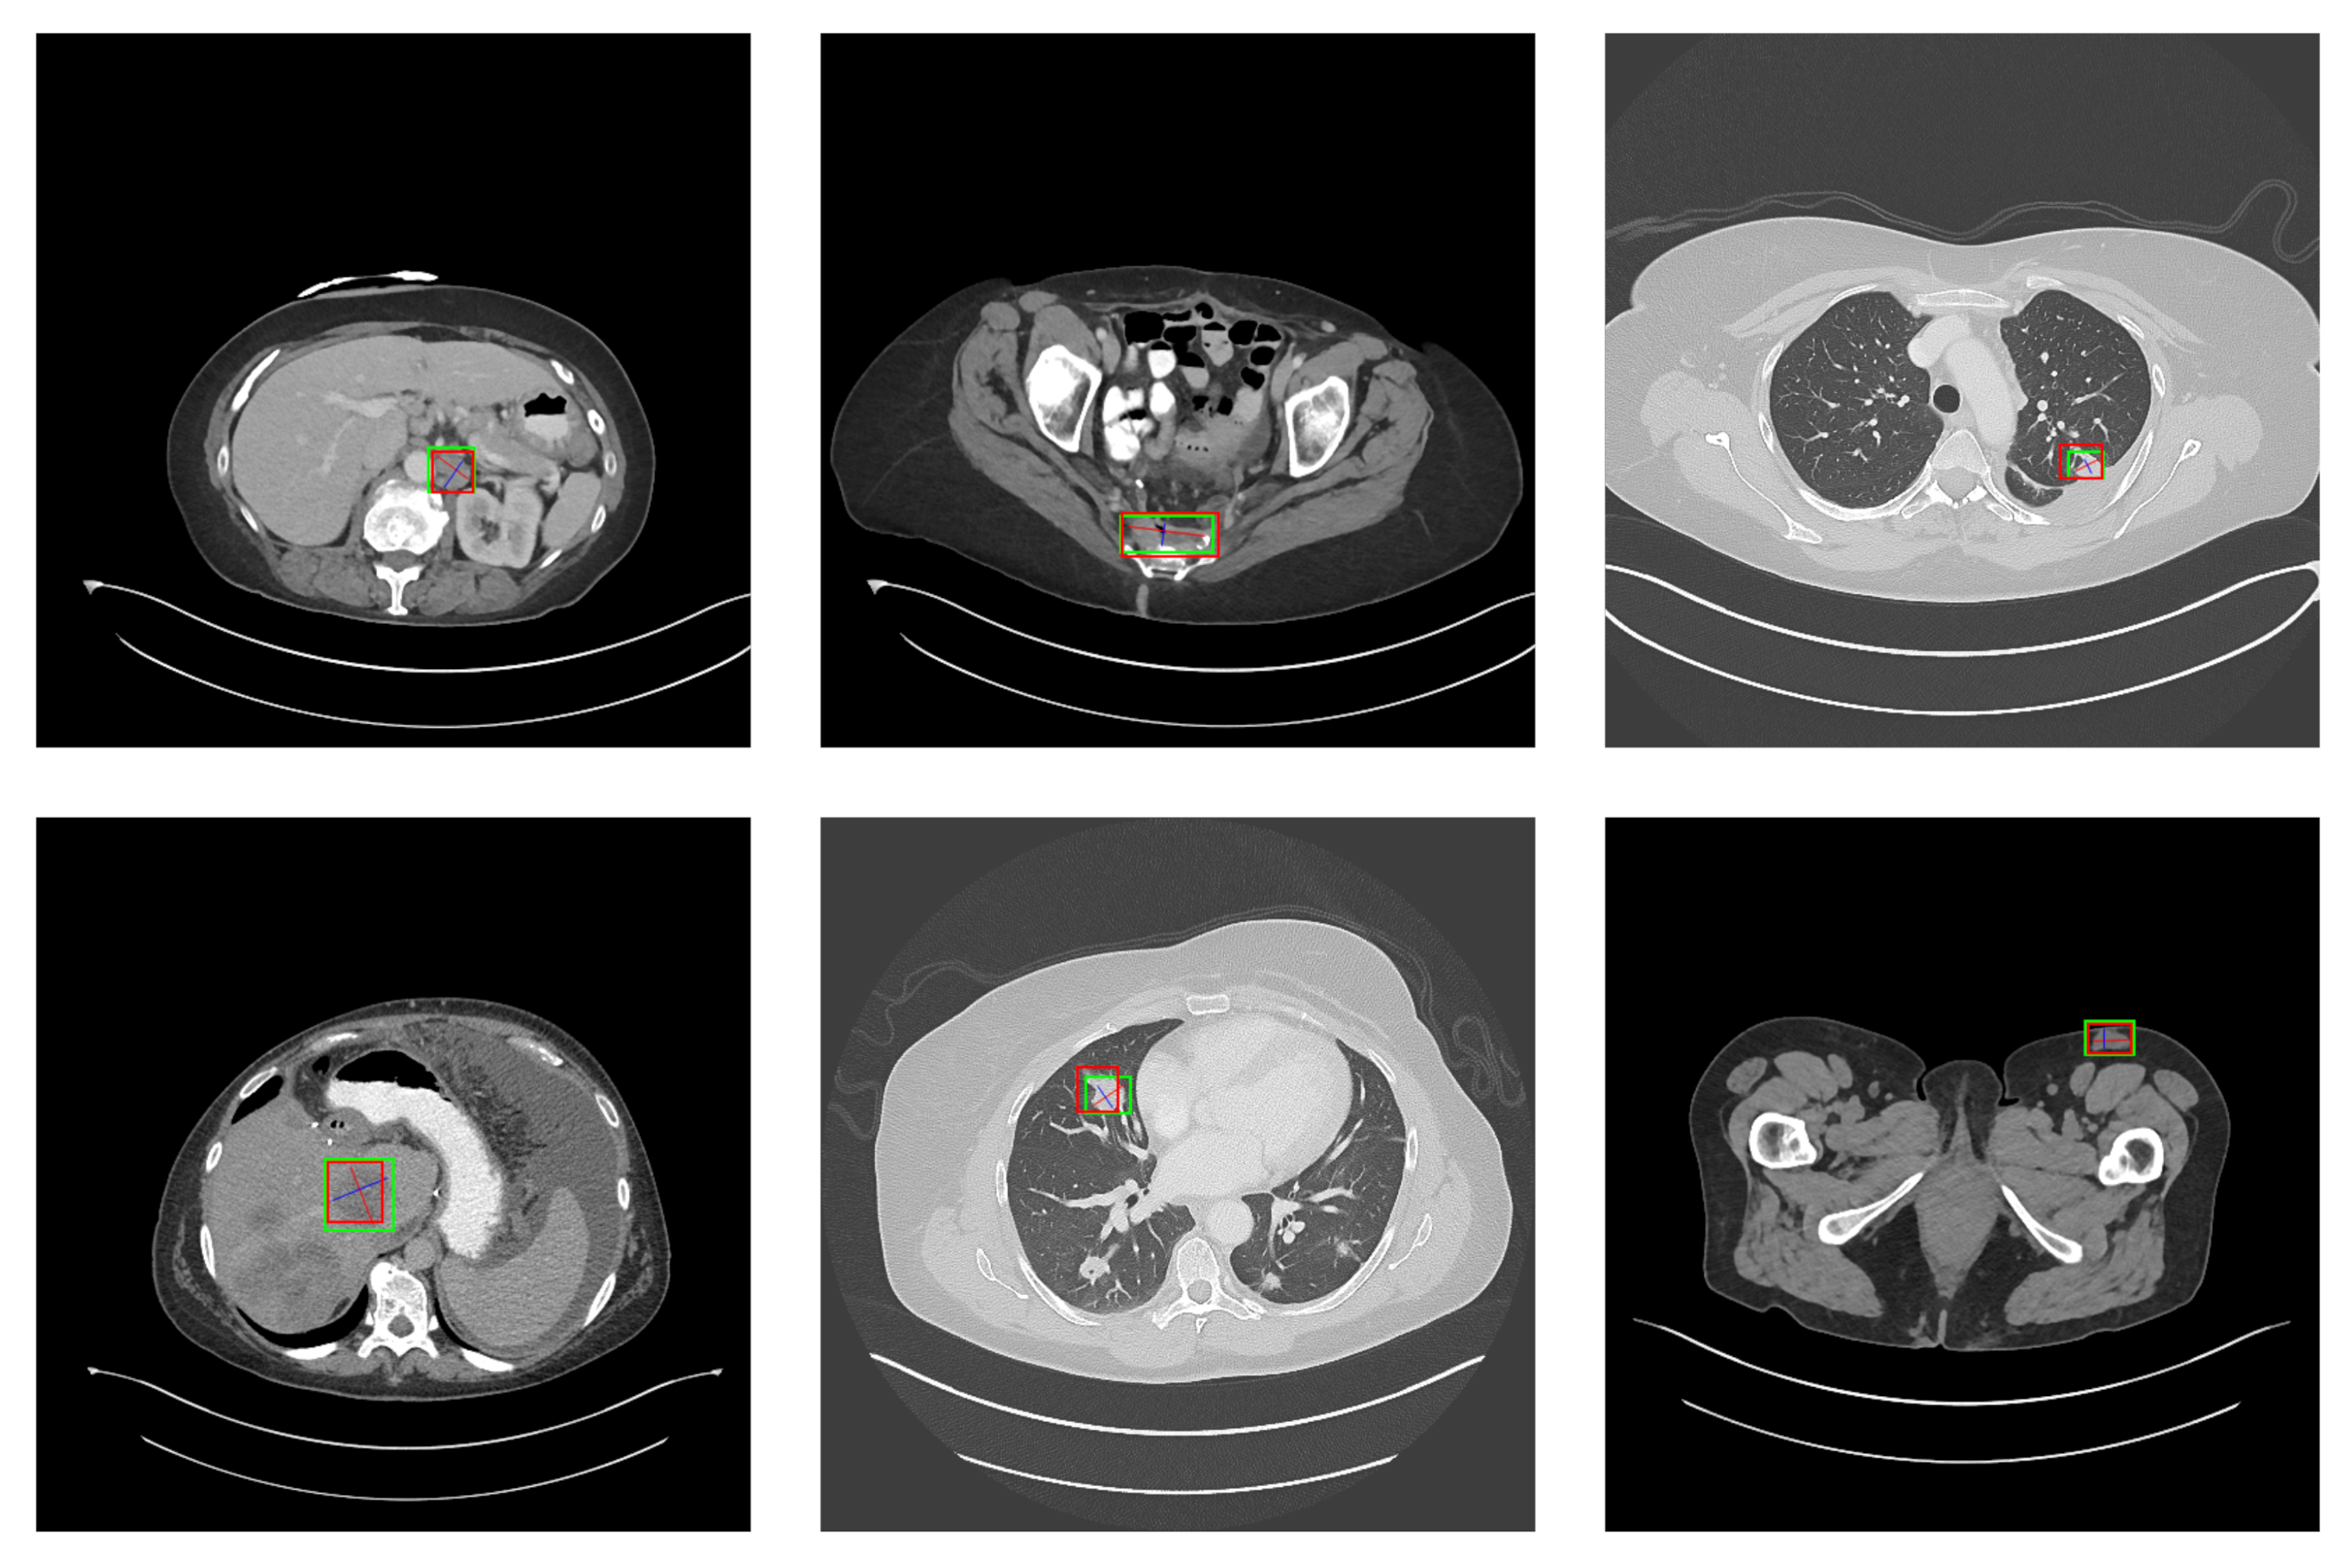

5.2. Detection Results

For further comparison, we extracted six images from the CT image series of DeepLesion. These images were taken from different sites of lesions and different areas of lesions, showing the detection results of the comparison model as comprehensively as possible. Figure 10, Figure 11, Figure 12, Figure 13, Figure 14, Figure 15, Figure 16, Figure 17, Figure 18 and Figure 19 show the detection results. All green boxes represent ground truth; red boxes denote predicted bounding boxes. It can be seen that Faster-RCNN performs very poorly on small lesions and lesions that are not easy to identify, while YOLO v3, YOLO v4, and SSD series perform relatively well. However, the aspect regression of the bounding box at small lesion locations is still not accurate. On the other hand, EfficientDet, Mask-RCNN, and YOLO v5 perform relatively well and detect lesions accurately. This may be related to the attention extraction module in these networks.

Figure 11.

The detection results of YOLO v4 in the DeepLesion dataset. The green box marks the location of the lesion.

According to Figure 10, Figure 11, Figure 12, Figure 13, Figure 14, Figure 15, Figure 16, Figure 17, Figure 18 and Figure 19, the proposed model produces the most comprehensive detection results compared to other models. However, there are still a few cases where the shortcomings of SGDN can be seen: the arrows in Figure 19 show that our model is still not accurate at the edge of the lesion. In addition, from these figures, we can see that all the comparison models perform very poorly at the site of arrow A. The difference between the predicted box and the ground truth given by our model at arrow A is the largest compared to other recognition results.